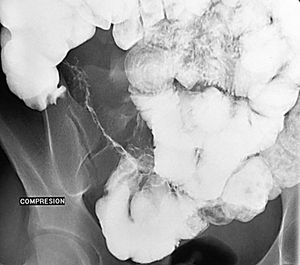

En la fase activa hay presencia de úlceras superficiales o aftoides (fig. 4). Pueden evolucionar haciéndose ulceraciones fisurantes longitudinales y transversales, dejando entre sí islotes de mucosa normal, constituyendo el concepto de patrón en "empedrado" (fig. 5).

Fig. 5.--Enfermedad de Crohn, fase activa inflamatoria. (A) Ulceraciones longitudinales y transversales que dejan entre sí islotes de mucosa edematosa, constituyendo el patrón en "empedrado" en el estudio baritado. (B) Correlación microscópica: ulceración fisurante rodeada del infiltrado inflamatorio, lesión claramente delimitada y rodeada de mucosa normal.